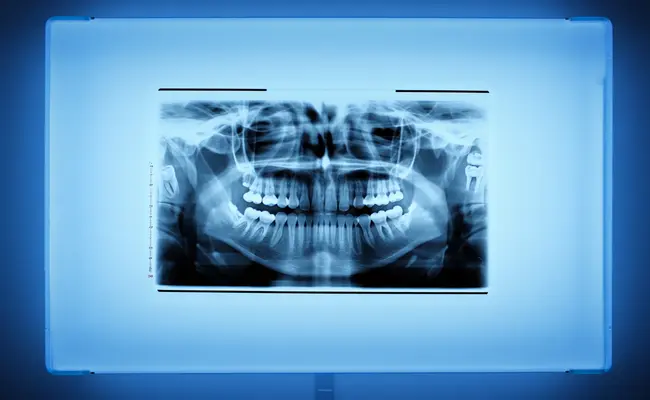

Here are some assessments you can expect during your initial evaluation visit:

8. Radiographs